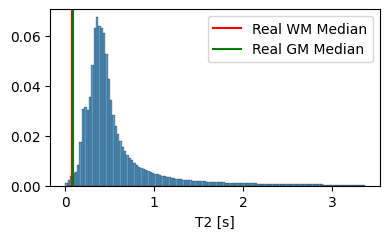

We set and based on the median of the property value distribution measured in real brain tissue [1], corresponding to a log-normal prior with a median of on T1 and a median of on T2.

3.1.2 Analysis of the Tissue Property Distribution

To ensure that our model can extrapolate to unseen modalities, it is crucial that the tissue property maps contain physically plausible values. In Figure 4, we compare the distribution of T1 and T2 values generated by our model to the average T1 and T2 values of white matter and grey matter in actual brain tissue. The results highlight the importance of the prior on the predicted T1 and T2 values, as it guides the model towards generating tissue properties that are, on average, more realistic. However, it is essential to note that the generated distribution includes tissue types beyond white matter and grey matter, such as cerebrospinal fluid and bones.